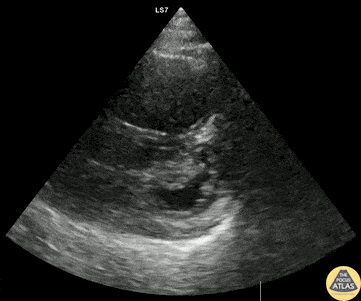

50s M with PMH COPD presented with dyspnea and increasing oxygen requirement. POCUS is shown here, demonstrating significant RV dilation, reduced RV function, and bowing of the septum concerning for pulmonary hypertension. Additional workup ultimately ruled out ACS and DVT/PE, and the patient was admitted for COPD exacerbation, and formal TTE confirmed a new diagnosis of pulmonary hypertension. Dr. Cailin Frank, Ultrasound Fellow, Denver Health Ultrasound Fellowship Dr. Anna Engeln, Denver Health Medical Center